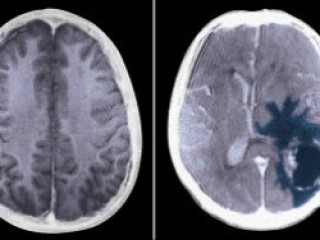

Beyin tümörlerinde yaşam süresi uzatıldı

Tıp teknolojisindeki gelişmelerden nöroşirürjinin de nasibini aldığını belirten Prof.Dr. Kuday, "Beyin cerrahisi alanında kullanılan gelişmiş MR'lar var. Beyinin yapısını, bölümlerini ve tümörün yerini görebiliyoruz. Bu sayede ameliyatta nereye dokunup nereye dokunmayacağımızı biliyoruz ve çok az zararla ameliyatlardan çıkabiliyoruz. Bu teknoloji ülkemizde var. Değişik bir MR şeklidir bu. Yakın bir zamanda da sadece şekline bakarak, biyopsi almadan tümörün cinsini söyleyebileceğiz" şeklinde konuştu. Günümüzde sadece teşhiste değil tedavide de önemli aşamalar kat edildiğini ifade eden Prof. Dr. Kuday, bunun da hastaların yaşam süresine önemli katkı sağladığını söyledi. Prof. Dr. Kuday, sözlerine şöyle devam etti:

Teknolojiler sayesinde beyin tümörlerinde yaşam süresinin uzadığını belirten Prof. Dr. Kuday, "Bazı tümörler var ki glial tümörler diyoruz genel bir başlık altına koyduğumuzda bu tümörlerin bulunduğu kişiler kısa yaşar. Yani en fazla 8 ay, bilemediniz 2 sene. Ama şimdi onların içinde bile bazı tümörler var ki hastalar uzun yaşatılabiliyor. Çünkü bu tümörlerin de kendi içinde farklı türevleri, farklı yapıları hassasiyetleri var ve buna yönelik ümmin sistemi geliştiren ilaçlar bazı reseptörler bulundu. Buna uygun ilaçlar verilerek yaşam süresi biraz daha uzatıldı" ifadelerini kullandı.